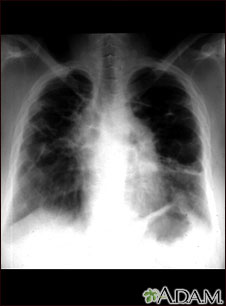

Sarcoide, etapa IV; rayos X de tórax

La placa muestra un sarcoide avanzado, cicatrización de los pulmones (bandas claras) y la formación de cavidades (áreas oscuras en la parte superior derecha).